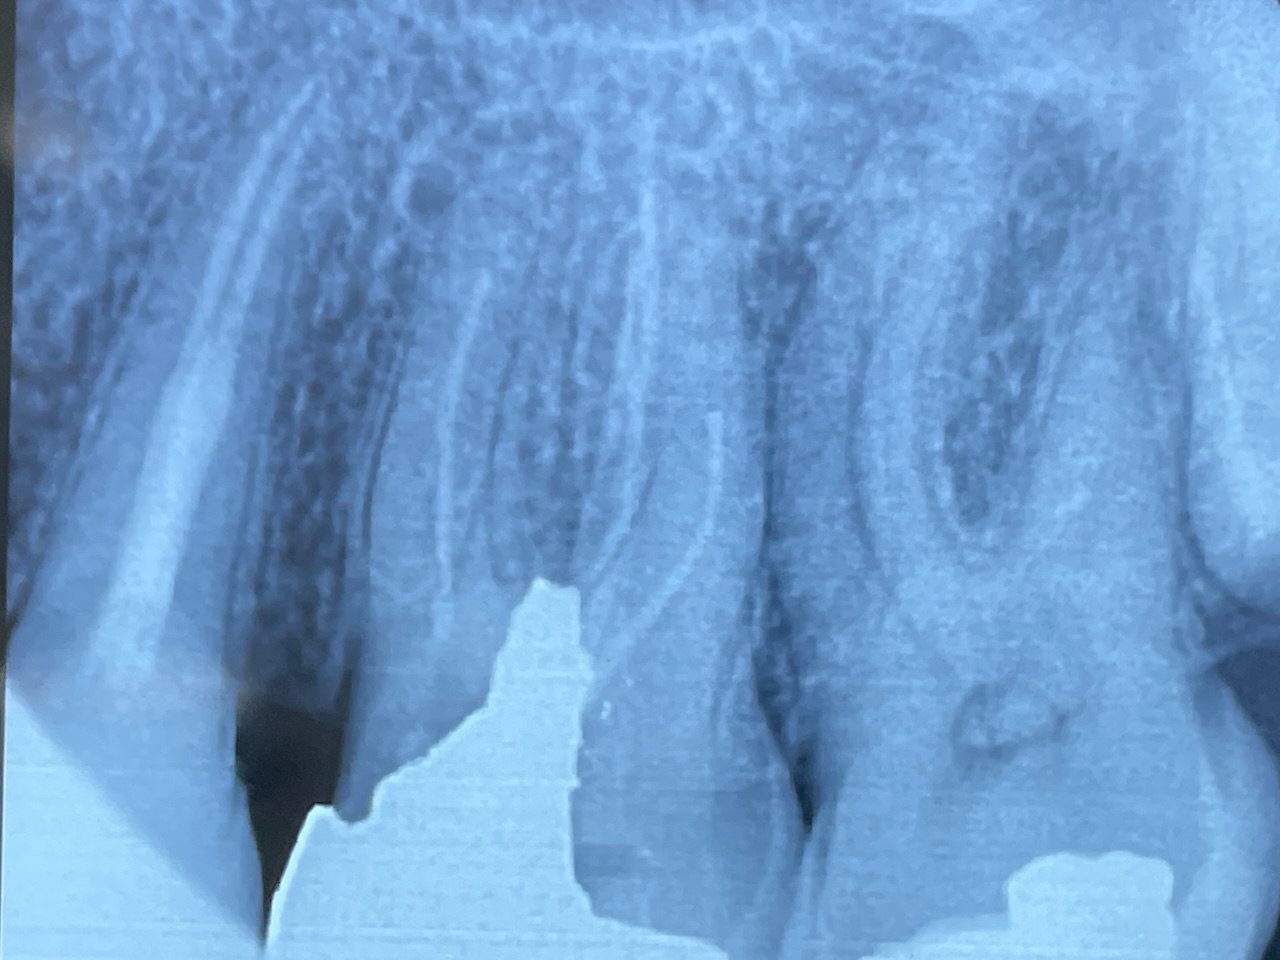

2. What option cannot be selected for root canal treatment of tooth # 2.6?